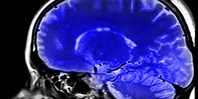

Стереотаксический манипулятор — главная часть хирургического комплекса для операций на глубоких структурах мозга. Разработчики подчеркивают, что это первый отечественный действующий образец такого манипулятора. Параллельно инженеры занимались созданием автоматизированного криогенного деструктора. Его задача — убирать патологии глубоких структур мозга посредством высокоизбирательного, точечного низкотемпературного воздействия. Так, рабочий участок зонда можно охладить до заданной температуры для уничтожения опухолей холодом.